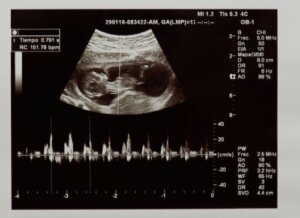

Med hjerteslag refererer vi til antall ganger hjertet trekker seg sammen i løpet av ett minutt. Fosterets hjertefrekvens kan identifiseres i de første ukene av svangerskapet ved hjelp av en ultralyd eller en monitor kjent som doppler.

Først vil ultralydteknikeren vurdere om hjerteslag faktisk er tilstede, og dermed kontrollere fosterets vitalitet. I tillegg vil de evaluere hvor mange ganger hjertet slår i løpet av ett minutt. Verdiene som anses som normale i fosterstadiet er mellom 120 og 160 slag per minutt.